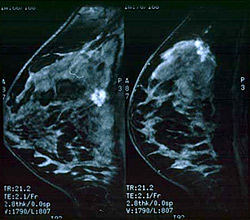

3) Μαστογραφία αναλογική ή ψηφιακή, (με ή χωρίς Υπερηχογράφημα και Μαγνητική τομογραφία μαστών)

Τα κλασσικά σημεία καρκίνου στην μαστογραφία είναι οι ακτινοειδείς προσεκβολές στην περιφέρεια του όγκου και / ή η παρουσία συρρεουσών, λεπτών ή ποικιλόμορφων αποτιτανώσεων. Είναι βεβαίως πιθανό σε έναν αψηλάφητο καρκίνο στην μαστογραφία, να αναδειχθεί και ένας δεύτερος καρκίνος στον ίδιο ή στον άλλο μαστό.

Συμπληρωματικό της μαστογραφίας στη διάγνωση είναι επίσης το Υπερηχογράφημα, το οποίο ελέγχει το περίγραμμα του όγκου (στην περίπτωση καρκίνου είναι ασαφές) και ιδιαίτερα το έγχρωμο υπερηχογράφημα, το οποίο μπορεί να καταδείξει αυξημένη αιμάτωση-αγγείωση της περιοχής στην περίπτωση καρκίνου.

Ακόμα πιο εξειδικευμένη εξέταση είναι και η Μαγνητική μαστογραφία σε ειδικά διαφοροδιαγνωστικά προβλήματα.